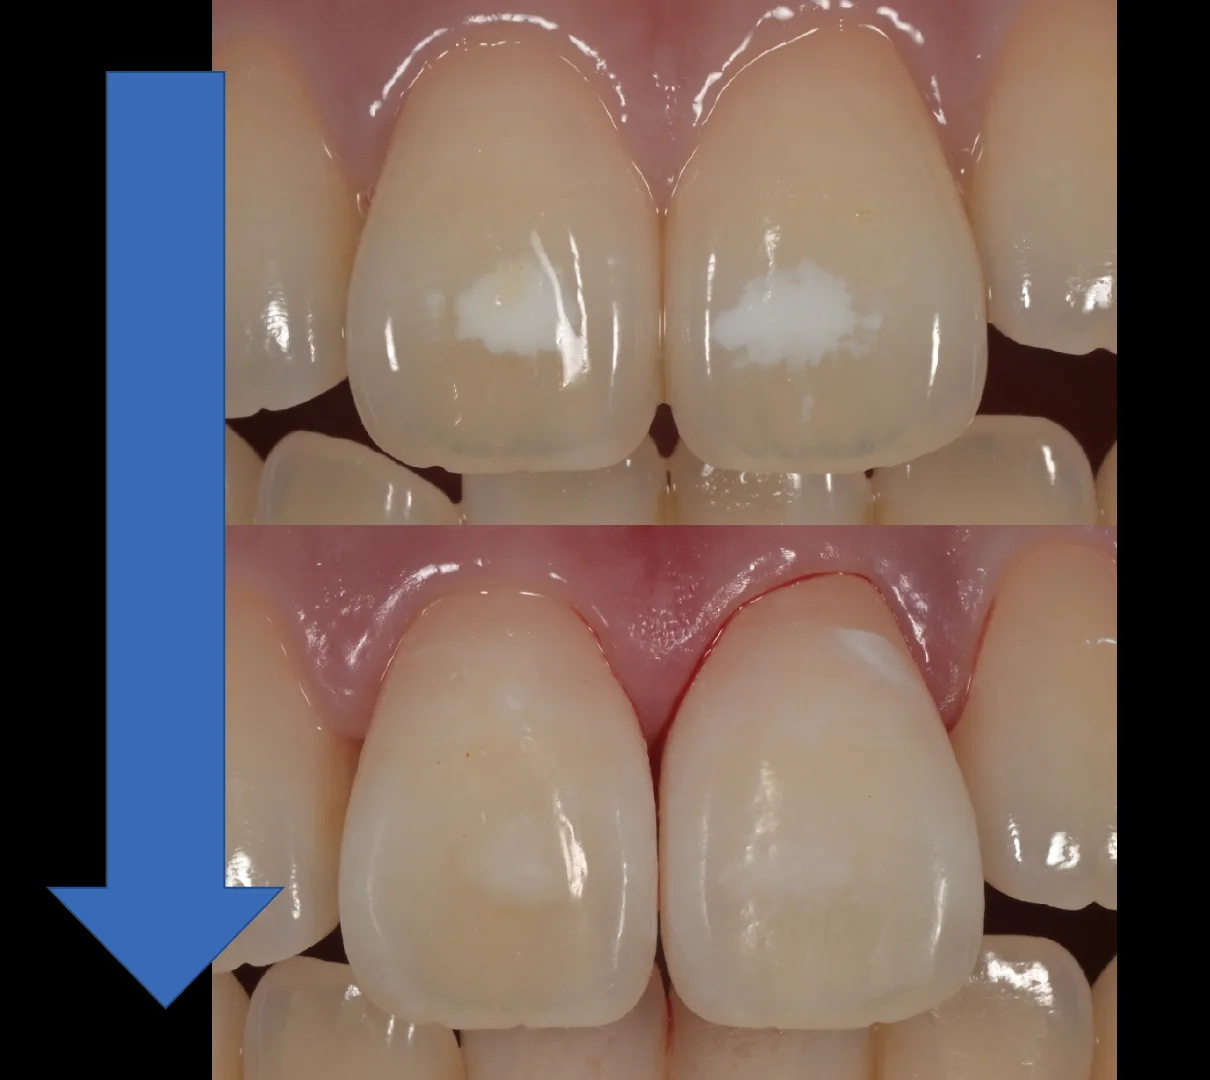

今回は個人的には色を消しきれていないため、あまり上手くいかなかったケースです。

ただ患者さんに見せて確認していただいたところ、これだけ消えていれば大丈夫、歯を削る方がもったいないとのことでしたので、今回はこのまま終了することとなりました。

術前術後です。

従来は切削が必要だった症例に対して、歯を削る量を抑えて対応できる場合があるのがICONの特徴のひとつと考えております(症例によって適応や効果には差があります)。仮に十分な効果が得られなかった場合でも、私の専門領域であるダイレクトボンディングへ移行できる体制を取っているため、無駄の少ない処置選択ができていると感じています。

色は若干残ってしまいましたが、患者さん本人はホワイトスポットが気にならないレベルに薄くなって非常に喜んでいただけました。